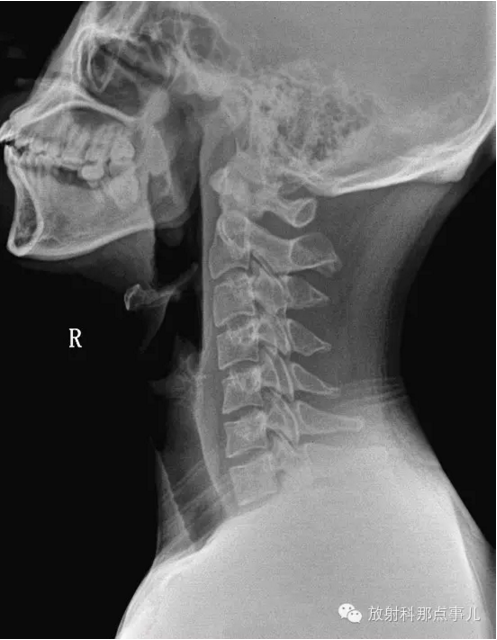

2、侧位片

①曲度的改变:颈椎发直、生理前突消失或反弯曲,除病人的投照位置、投照角度等技术因素之外,可能会有几种原因:

第一、颈部软组织发生急性扭伤或纤维织炎,疼痛剧烈或有肌肉紧张时,可以影响颈部的正常姿势及活动。

第二、颈椎间盘突出或颈椎病有神经根刺激症状者,病变节段的脊椎固定不动或椎间隙有前窄后宽而出现后突现象。

第三、由于颈椎间盘变性部位不同,程度不一,也可发生曲度的改变及局部旋转或偏歪现象而表现为局部棘突偏歪;关节突、椎根切迹及椎体后缘呈双影现象。在侧位片,以下三种情况有临床意义:

a:一个或两个颈椎椎间小关节突呈有双影,称为双凸现象;椎根切迹呈有双影,称为双凹现象;椎体后缘呈有双影,称为双边现象,而上下颈椎却显影正常,表示其颈椎有旋转现象。

b:上部颈椎显影正常,而下部颈椎呈现双凸、双边、双凹现象;或下部正常而上部有类似的变化,表示其交界部有旋转现象。

c:颈脊椎的一个或两个脊椎显影正常,而其部分有双凸、双凹、双边现象,表示显影正常的颈椎有旋转现象,如全部颈脊椎的后部呈现双凸、双凹、双边现象,则为投照不当的原因,无临床意义。

②有异常活动度:在颈椎过伸过屈侧位X线片中,可以见到椎间盘的弹性改变,弹性好者,相对稳定,其活动度小并与上下椎间盘相似;严重者可见有滑椎现象,表现为各颈椎前后缘排列不齐。这种现象对病变的椎间盘的定位诊断及了解手术以后植骨情况有帮助。

③骨赘:椎体前后接近椎间盘的部位都能产生骨赘及韧带钙化。后方的骨赘容易引起症状。但骨赘的大小并非与临床症状的严重程度成正比,因而骨赘不大明显而脊髓受压迫明显、骨赘大而临床症状不明显者均可发生。

④椎间盘变窄:椎间盘因为髓核突出、椎间盘含水量减少而发生纤维变性而变薄,表现在X线平片上椎间盘变窄。

⑤半脱位及椎间孔变小:椎间盘变性以后,椎体间的稳定性较差,椎体发生半脱位,或称之为滑椎。椎体的半脱位引起椎间孔的横径和椎管的前后径变小而产生临床症状。

⑥项韧带钙化:临床上当项韧带钙化时,与其相对应的椎间盘早已出现退行性的变化。这是因为椎间盘变性以后,相应节段的项韧带负荷较多的缘故。项韧带骨化之前,局部韧带组织经历退变及软骨化的阶段,临床上可以触及局部有硬化,而X线平片却不能显示出来。